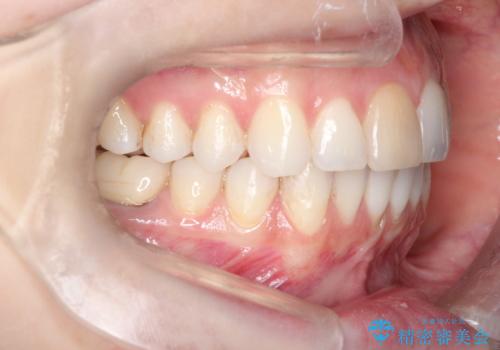

インビザラインによる非抜歯での八重歯の矯正

- 左上の八重歯と、上の歯のがたつきを主訴に来院されました。

上の奥歯を後方に移動させてスペースを作るのと、歯と歯の間をわずかに削り歯を並べる計画としました。

非常に強力的な患者様であったので、上下の正中も合わせ、ガタガタも改善することができました。